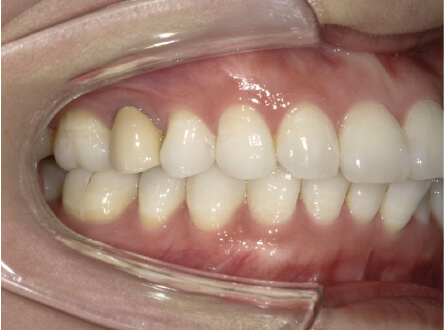

叢生の症例

9歳

女性

相談内容

マイオスマイルからの移行

カウンセリング・診断結果

上11捻転、上33スペース不足、インビザで歯列矯正

治療内容・方法

全額アライナー矯正 クリアコレクト

術後の経過・現在の様子

リンガルアーチ使用

治療のリスク

痛み・歯根吸収・歯肉退縮・虫歯・後戻り

費用・治療期間

(マウスピース矯正のみ)440,000円+220,000円 月々27,500円、9ヶ月+myo1年10ヶ